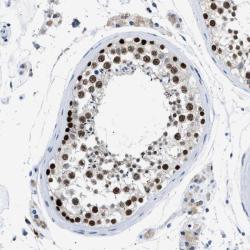

Supportive validation

- Experimental details

- Immunohistochemical staining of human testis shows strong nuclear positivity of cells in seminiferus ducts.

- Validation comment

- Two independent antibodies targeting one protein yielding similar staining patterns. Staining pattern consistent with experimental and/or bioinformatic data.